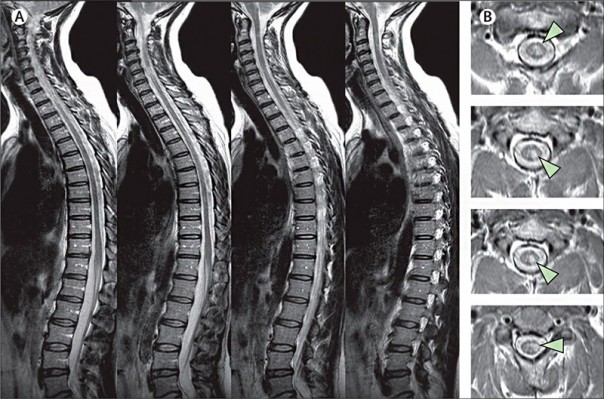

- Исключение опухолей спинного мозга и позвоночного столба. На детальных МРТ-снимках можно определить место опухоли, объем и связь с нейронной осью. С помощью изображений исследуют морфологические и гистологические особенности опухоли, делают выводы о ее природе. Если речь идет об опухолях позвоночника, то с помощью МРТ можно узнать ее размеры, спрогнозировать рост и сдавление спинного мозга.

- Исключение артериовенозных мальформаций: МРТ имеет значение для диагностики интрамедуллярной артериовенозной мальформации. Методика магнитно-резонансной томографии гораздо эффективнее, чем ангиография и КТ.